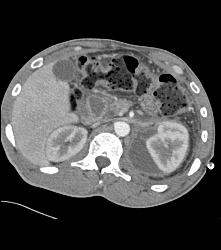

Perirenal Hematoma